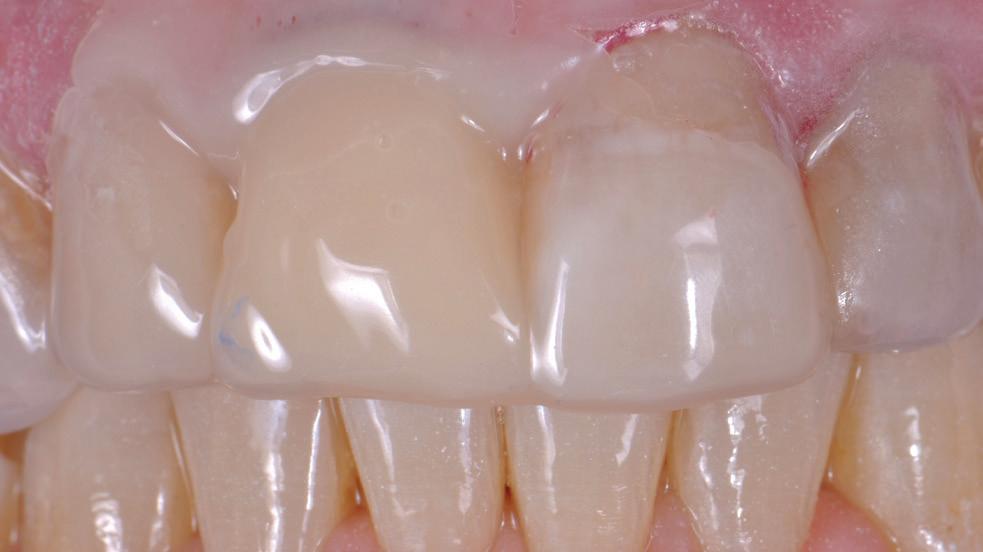

Life can have its ups and downs: Aesthetic incisal restorations after two spontaneous fractures